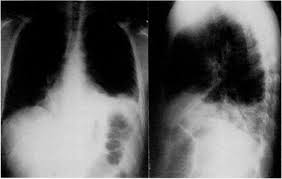

The Shaggy Esophagus Springerlink

The Shaggy Esophagus Springerlink from media.springernature.com

Behr j, kreuter m, hoeper mm, wirtz h, klotsche j, koschel d, andreas s, claussen m, grohé c, wilkens h, randerath w, skowasch d, meyer fj, kirschner j. A recent review reveals 56 documented cases in the literature. Animals with mild esophagitis generally have a favorable prognosis. B from levine ms, woldenberg r, herlinger h, et al. Esophagitis may cause odynophagia and even esophageal hemorrhage, which is usually occult but can be massive. Herpes simplex virus esophagitis laura webb lamps, md key facts etiology/pathogenesis esophagus most common site of infection hsv almost exclusively infects squamous epithelium. Department of radiology of the loyola university medical center, usa. Hsv esophagitis has been described in immunocompetent hosts, however, it remains a rare entity.